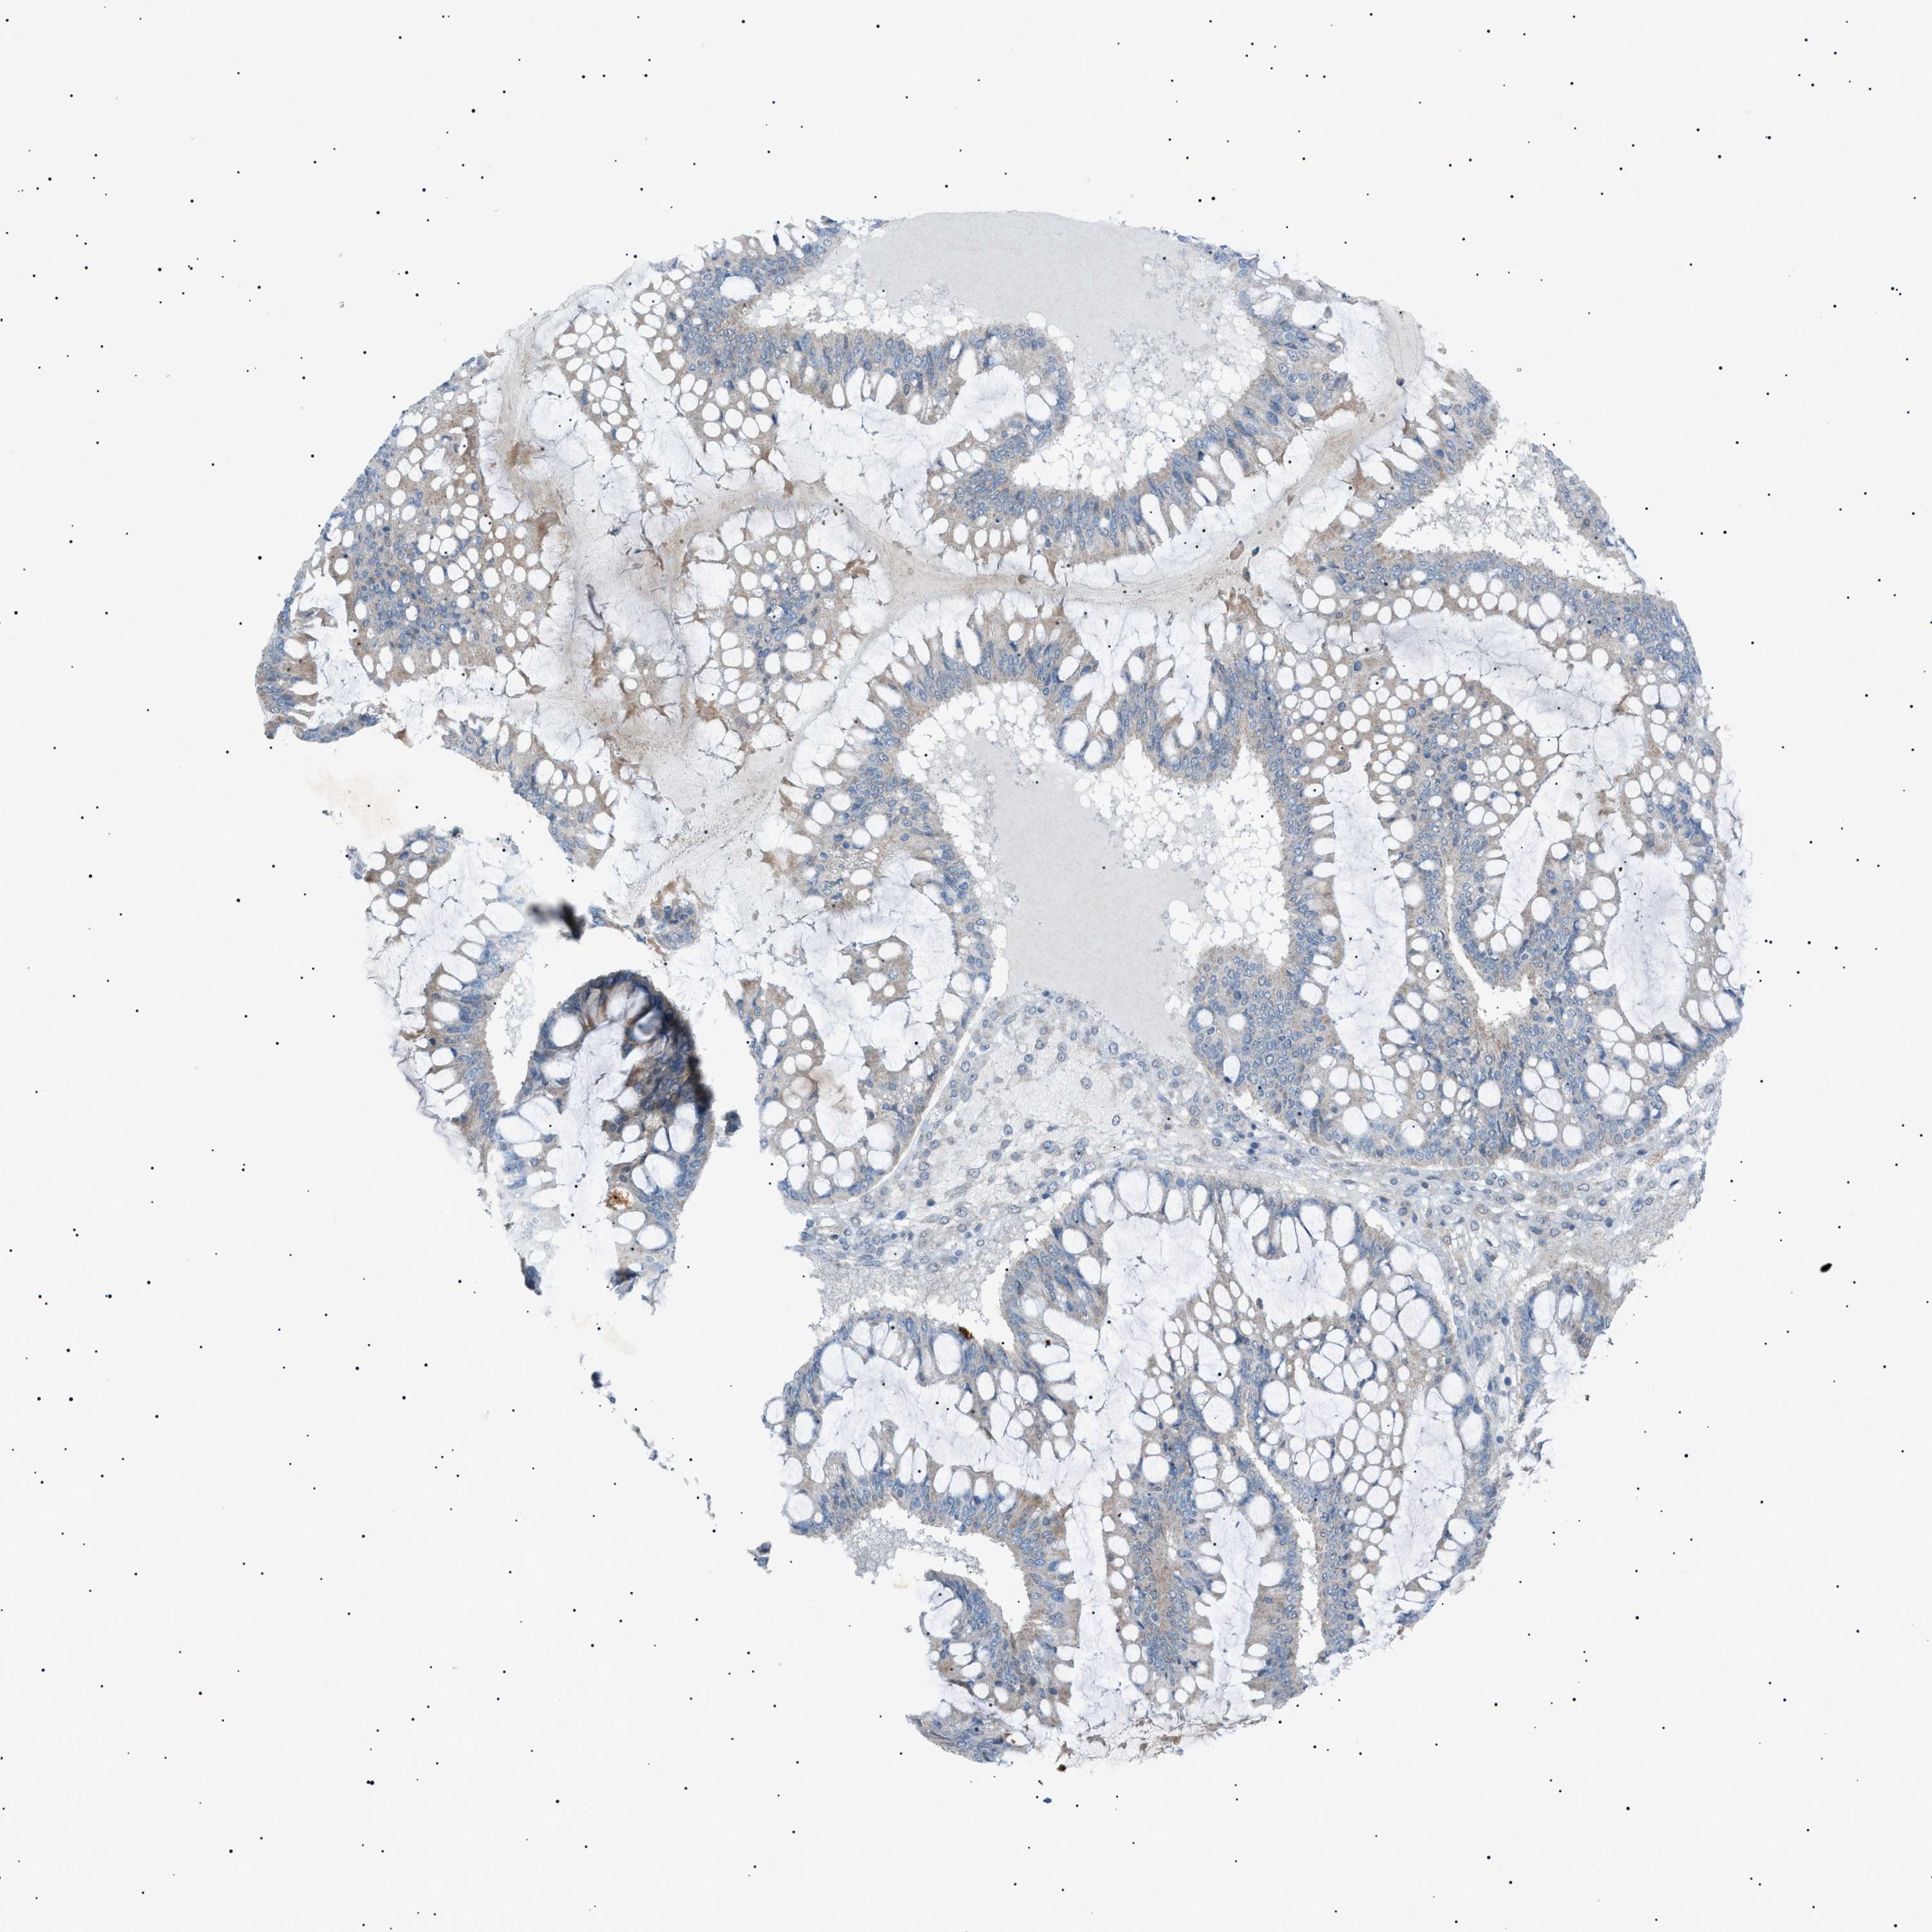

OVARIAN CANCER - Protein expressioni

A mouse-over function shows sample information and annotation data. Click on an image to view it in a full screen mode. Samples can be filtered based on level of antibody staining by selecting one or several of the following categories: high, medium, low and not detected. The assay and annotation is described here.

Note that samples used for immunohistochemistry by the Human Protein Atlas do not correspond to samples in the TCGA dataset.

Antibody stainingi

Antibody staining in the annotated cell types in the current human tissue is reported as not detected, low, medium, or high, based on conventional immunohistochemistry profiling in selected tissues. This score is based on the combination of the staining intensity and fraction of stained cells.

Each image is clickable and will lead to virtual microscopy that enables deeper exploration of all samples and also displays staining intensity scores, fraction scores and subcellular localization as well as patient and tissue information for each sample.

Antibody HPA001198

Antibody HPA002028

Antibody CAB016689

Antibody CAB080300

Cystadenocarcinoma, mucinous, NOS

Carcinoma, endometroid

Cystadenocarcinoma, serous, NOS

Carcinoma, NOS